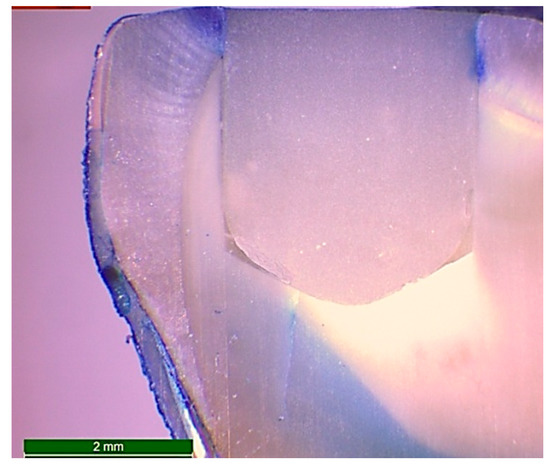

After the packing and curing of the resin composite according to the previously mentioned specimens’ grouping, the surfaces of the restorations were finished and polished using ascending grits (Soflex, 3M OralCare, St. Paul, MN, USA). Prepared specimens for microleakage testing were subjected to cycles of thermal fluctuations for the simulation of artificial aging using a thermocycler (Thermocycler THE-1100, SD Mechatronik, Germany) from 55 (±1) to 5 (±1) °C, with a dwell time of 30 s and a transfer time between each water bath of 10 s—for 5000 cycles. After the completion of thermo-cycling, the teeth were dried and double coated with a waterproof nail varnish along the whole surfaces except for 1 mm around the margins of the restoration. Then, the teeth were immersed in freshly prepared 1.0% methylene blue dye (Certistain, Merck, Darmstadt, Germany) for 24 h. The teeth were then rinsed thoroughly with running water and sectioned buccolingually along their long axes into two sections using an automated water-cooled diamond saw (EXAKT 300 CP Band System, Norderstedt, Germany). The specimens were examined for marginal leakage and dye penetration by using stereomicroscope (Wild Heerbrugg transmitted-light stand EB, Leica microsystem, Wetzlar and Mannheim, Germany) at a magnification of 15X (Figure 3). The scoring of dye penetration was done for marginal leakage (Figure 4) as follows:

Figure 3.

Microphotograph at 15X magnification of a longitudinal section of a restored standardized cavity in a sound molar after 5000 cycles of thermo-cycling and immersion in freshly prepared 1.0% methylene blue dye for 24 h in order to examine the marginal leakage by evaluation of the grade of dye penetration.